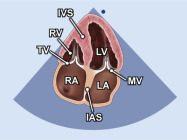

| 2.14. Mặt cắt 4 buồng từ mỏm |

||||||||

|

|

Cửa sổ siêu âm từ mỏm tim Mặt cắt 4 buồng

Bệnh nhân nằm nghiêng trái, xác định diện đập của mỏm tim, marker đầu dò hướng về giường bệnh |

Nhĩ trái (LA)

Van hai lá (MV) Thất trái (LV) Vách liên thất (IVS) Thất phải (RV) Van ba lá (TV) Nhĩ phải (RA) Vách liên nhĩ (IAS) |